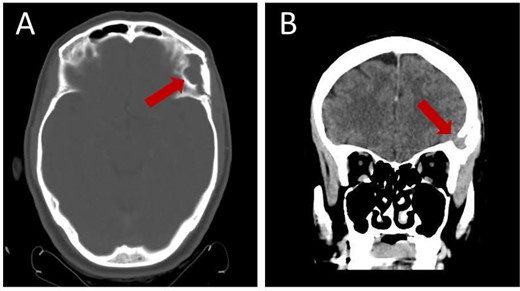

A follow-up brain CT 3 months after the operation illustrates resection with complete absence of residual tissue (Fig. 5).

Follow-up brain CT, 3 months post-operation, showing complete resection of the lesion without residual tissue: (A) axial view and (B) coronal view.